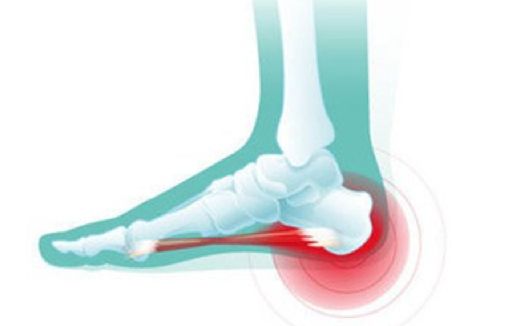

临床上在绝大多数患者脑海中已经认为某些部位的骨刺就是我们相关部位产生疼痛的原因。如膝关节有骨刺就会产生膝关节疼痛,跟骨有骨刺就会产生足跟痛。实际上,临床上约有一半的足跟痛病人并没有发现有“跟骨骨刺”,“跟骨骨刺”本身不会引起疼痛,只有当“跟骨骨刺”长期存在,且长“骨刺”的跟骨经过长期负重或局部负重过大,引起跟骨局部充血和产生无菌性炎症时,足跟才会产生疼痛,此时“骨刺”才成为致病的元凶。

如果患者是在治疗足部其他疾病时,拍摄 X 线片才发现跟骨长了“骨刺”,但没有症状,多不用紧张,更不用对它进行切除治疗。一般地说,对于临床上常见的像王阿姨所患的足跟痛,采取非手术疗法如口服中药或消炎止痛药物,配合药物外敷或中药外洗以及使用冲击波、小针刀等均可以获得不错的效果,对一些明确是跟骨骨刺引起的顽固性足跟痛经过正规的保守治疗仍然无效时可通过微创关节镜行跟骨骨刺切除以及局部的松解也可取得良好的临床效果。